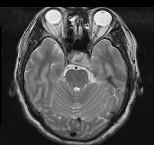

问题 男,41岁,头昏伴头痛1年,请根据所提供图像,选择最可能的诊断()

选项 A.(鞍区)脑膜瘤 B.(鞍区)颅咽管瘤 C.(鞍区)生殖细胞瘤 D.(鞍区)转移瘤 E.(鞍区)垂体腺瘤

答案 E